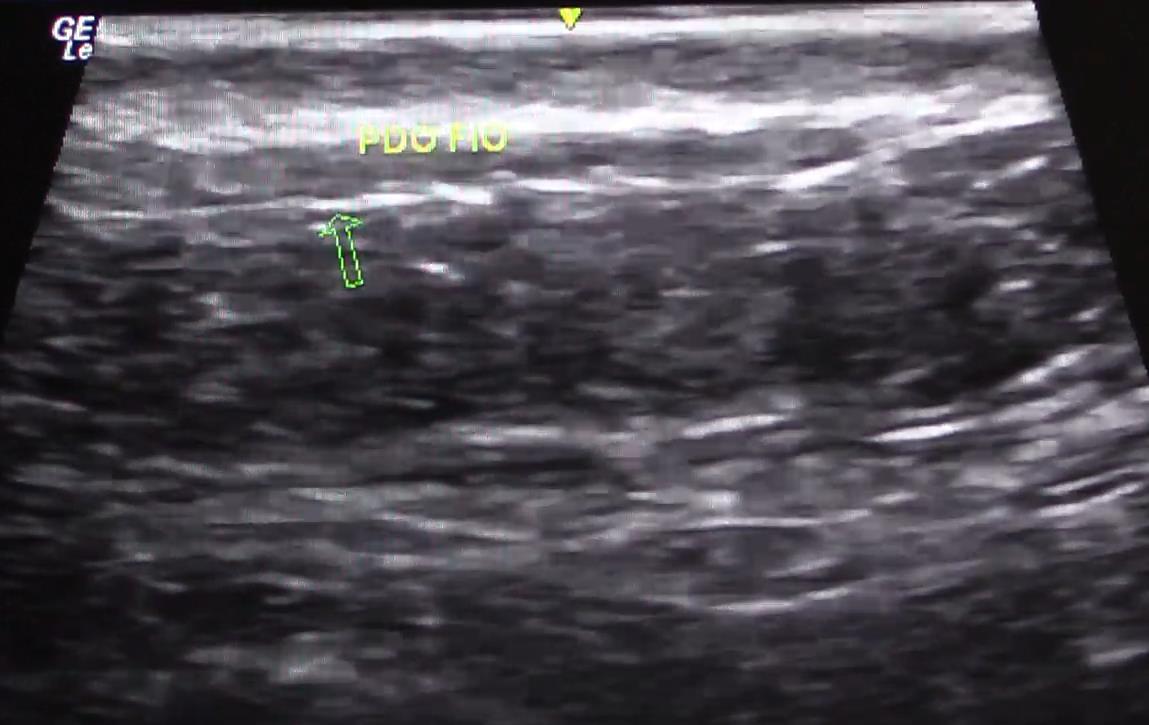

DISTÂNCIA DA DERME 3mm Representação de plano de aplicação com fio canulado. Fonte: Ultrassom realizado pela Dra. Cristiane Ribeiro, radiologista e dermatologista.

Fonte: Ultrassom realizado pela Dra. Cristiane Ribeiro.